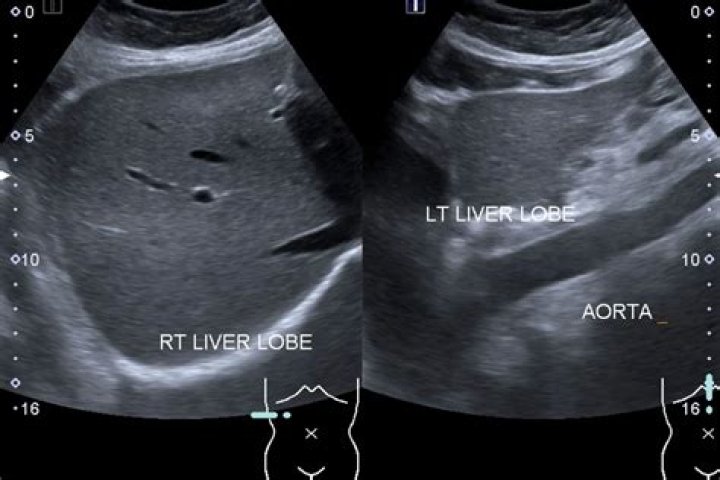

Tests that create pictures of the inside of the body are known as imaging scans. Ultrasound is commonly used to look for primary liver cancer and also to monitor people with cirrhosis. Ultrasound alone cannot confirm a diagnosis of liver cancer, so you will also have one or more other scans.

Dilated bile ducts and any fluid near the liver (ascites, fluid collections) will also typically show up on a liver ultrasound. Other organs, including the gallbladder, right kidney, and at least a portion of the pancreas are often seen as well.

At the start of the exam, a hypoallergenic, odor-free, warm gel will be gently lathered onto the abdomen. The sonographer who will be performing the examination will move a transducer around the abdomen and rib cage area. The transducer will take pictures of your liver and surrounding organs, producing the ultrasound.